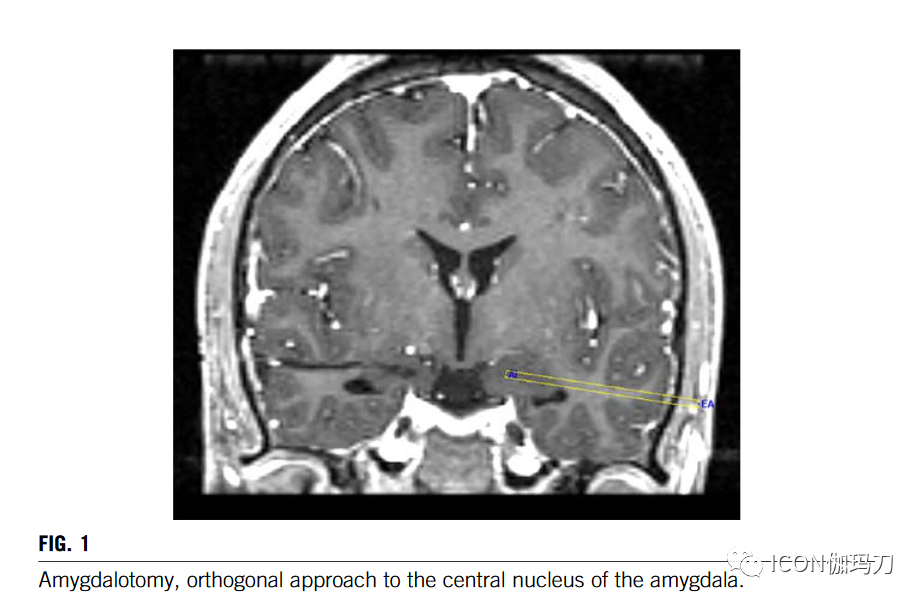

内囊毁损术的坐标为:x-双侧至中线19-21mm, y-0和z-0与前联合相关,这大致对应于内囊的中部区域,在壳核内侧边缘的后区水平(he coordinates for the capsulotomy were: x-19–21 mm bilateral to midline, y-0,and z-0 related to anterior commissure, which corresponds approximately to the middle area of the capsules at the level of the posterior region of the medial edge of the putamen)。对于杏仁核毁损术、扣带回毁损术和终纹毁损术,可以通过直接可视化来鉴别。在所有情况下,电极的进入点都是根据血管的顺序选择避开路径中的血管。采用单极电极(直径2 mm,长度4 mm)热损损法,在每个毁损部位温度70℃,持续90 s。在距靶点近端0、2、3和5毫米处的每处内囊上分别进行4次毁损。杏仁核、扣带回和终纹的毁损是在距靶点0和2毫米处形成的。电极的导入通过双侧终纹、扣带回和内囊毁损的两个钻孔进行,杏仁核采用我们开发的轨迹,通过颞叶钻孔进行正交入路(图1)。术后即刻,患者仍处于全身麻醉下,通过CT扫描确认毁损的正确位置和无并发症。